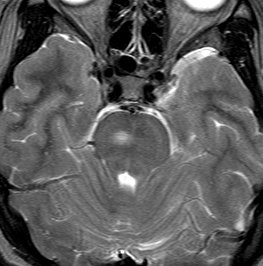

脳幹部のUBOです,大きくなると脳幹部神経膠腫に間違えられることがあります

脳幹部グリオーマと間違えそうなもの

3歳の時に,MRIで脳幹部から小脳のグリオーマを疑われて受診しました。橋が腫れて右小脳にもグリオーマのような白い影があります。でもこれは,NF-1のUBOの大きなものです。びまん性正中グリオーマと誤診されて放射線治療を受けてしまった子供もみたことがあります。治療しなくても縮小していくので,何もしないで経過観察します。右側のMRIは13年後のものです。ほとんど消失しています。